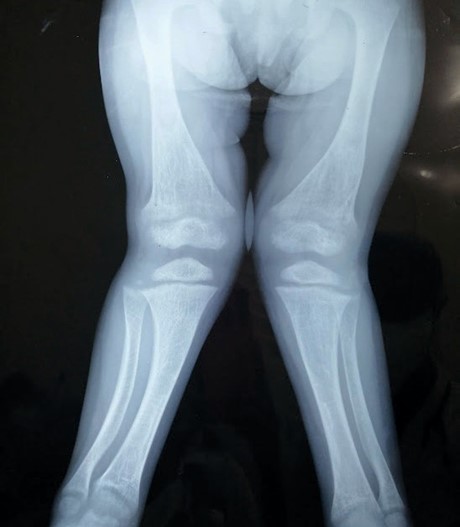

Figura 5. Rx Ambos Miembros Inferiores AP

Fuente: Expediente clínico. Hospital Infantil Dr. Robert Reid Cabral.

Deformidad en valgo con presencia de alteración de la morfología de las metáfisis femorales, tibiales y en ambos peronés en forma de copa, con disminución de la densidad ósea principalmente en 1/3 distal de ambos fémures en relación con desmineralización de estos. Disminución de la amplitud de la línea de crecimiento a nivel femoral y tibial con visualización de los núcleos de osificación femorales, tibiales y peroneos disminuidos de tamaño.